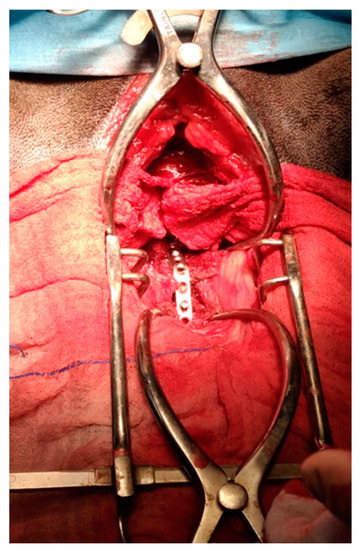

2.2. Surgical Technique